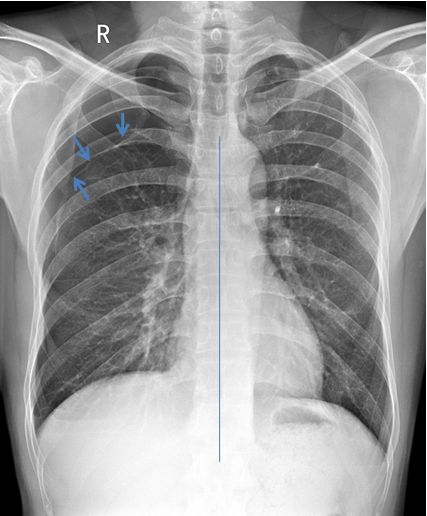

病例4患者的X线胸片

患者右肺上叶可见肺叶压缩带边缘,肺叶压缩约5% (蓝色箭头)。